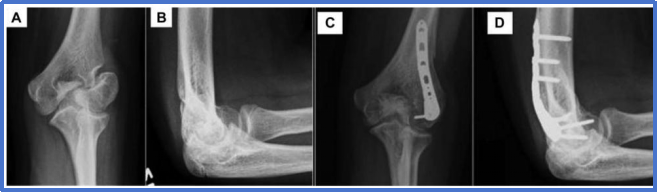

骨不连

最主要并发症,定义为伤后12周骨折未愈合,发生率1%-5%;诱因包括漏诊、非手术治疗迟发移位、手术治疗再移位/固定后残留移位>1mm;临床表现为肘外侧压痛、外翻畸形、肘关节活动受限;治疗依移位程度选择,轻度移位可行经皮加压螺钉固定(伤后16周内手术效果佳),重度移位需切开复位+植骨,合并外翻畸形者需联合截骨矫正。

图19 一名 13 岁男性患者,7 年前左肘关节骨折曾行石膏固定治疗;A 正位 X 线片示肱骨外髁骨折不愈合;该患者肘关节活动度正常,但存在疼痛症状,且疼痛限制了其体育运动。B 侧位 X 线片示骨折块对位异常(呈屈曲位)。C 行原位钢板固定联合髂骨植骨术后的正位 X 线片。D 术后侧位 X 线片。